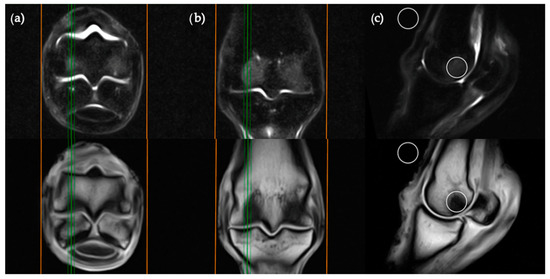

The transverse image located two slices distal to the level of the physeal vasculature was chosen for the transverse plane measurements (Figure 2). Three ROIs were placed; centrally within the distal palmar/plantar margin of the lateral and medial condyles and immediately between these ROIs at the palmar/plantar aspect of the sagittal ridge. The background ROI was placed at the lateral or medial surface of the limb, at the palmar/plantar half of the condyles and in alignment with the three intraosseous ROIs.

Figure 2. STIR FSE (top row) and T1W GRE (bottom row) MRI images in (a) transverse; (b) frontal and (c) sagittal planes; demonstrating the location of ROI placements in a transverse plane. The green lines on the frontal and sagittal images show the standardized orientation and location of the transverse slice for ROI placement. The orange lines show the extent and orientation of all the transverse slices acquired in the MRI study.